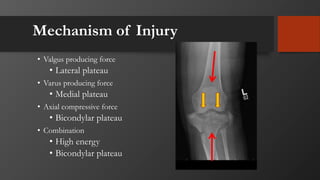

Mechanism of Injury

• Valgus producing force

• Lateral plateau

• Varus producing force

• Medial plateau

• Axial compressive force

• Bicondylar plateau

• Combination

• High energy

• Soft tissue injury